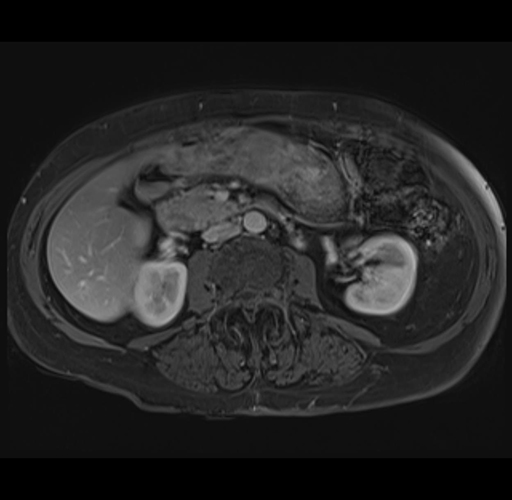

MRI T1